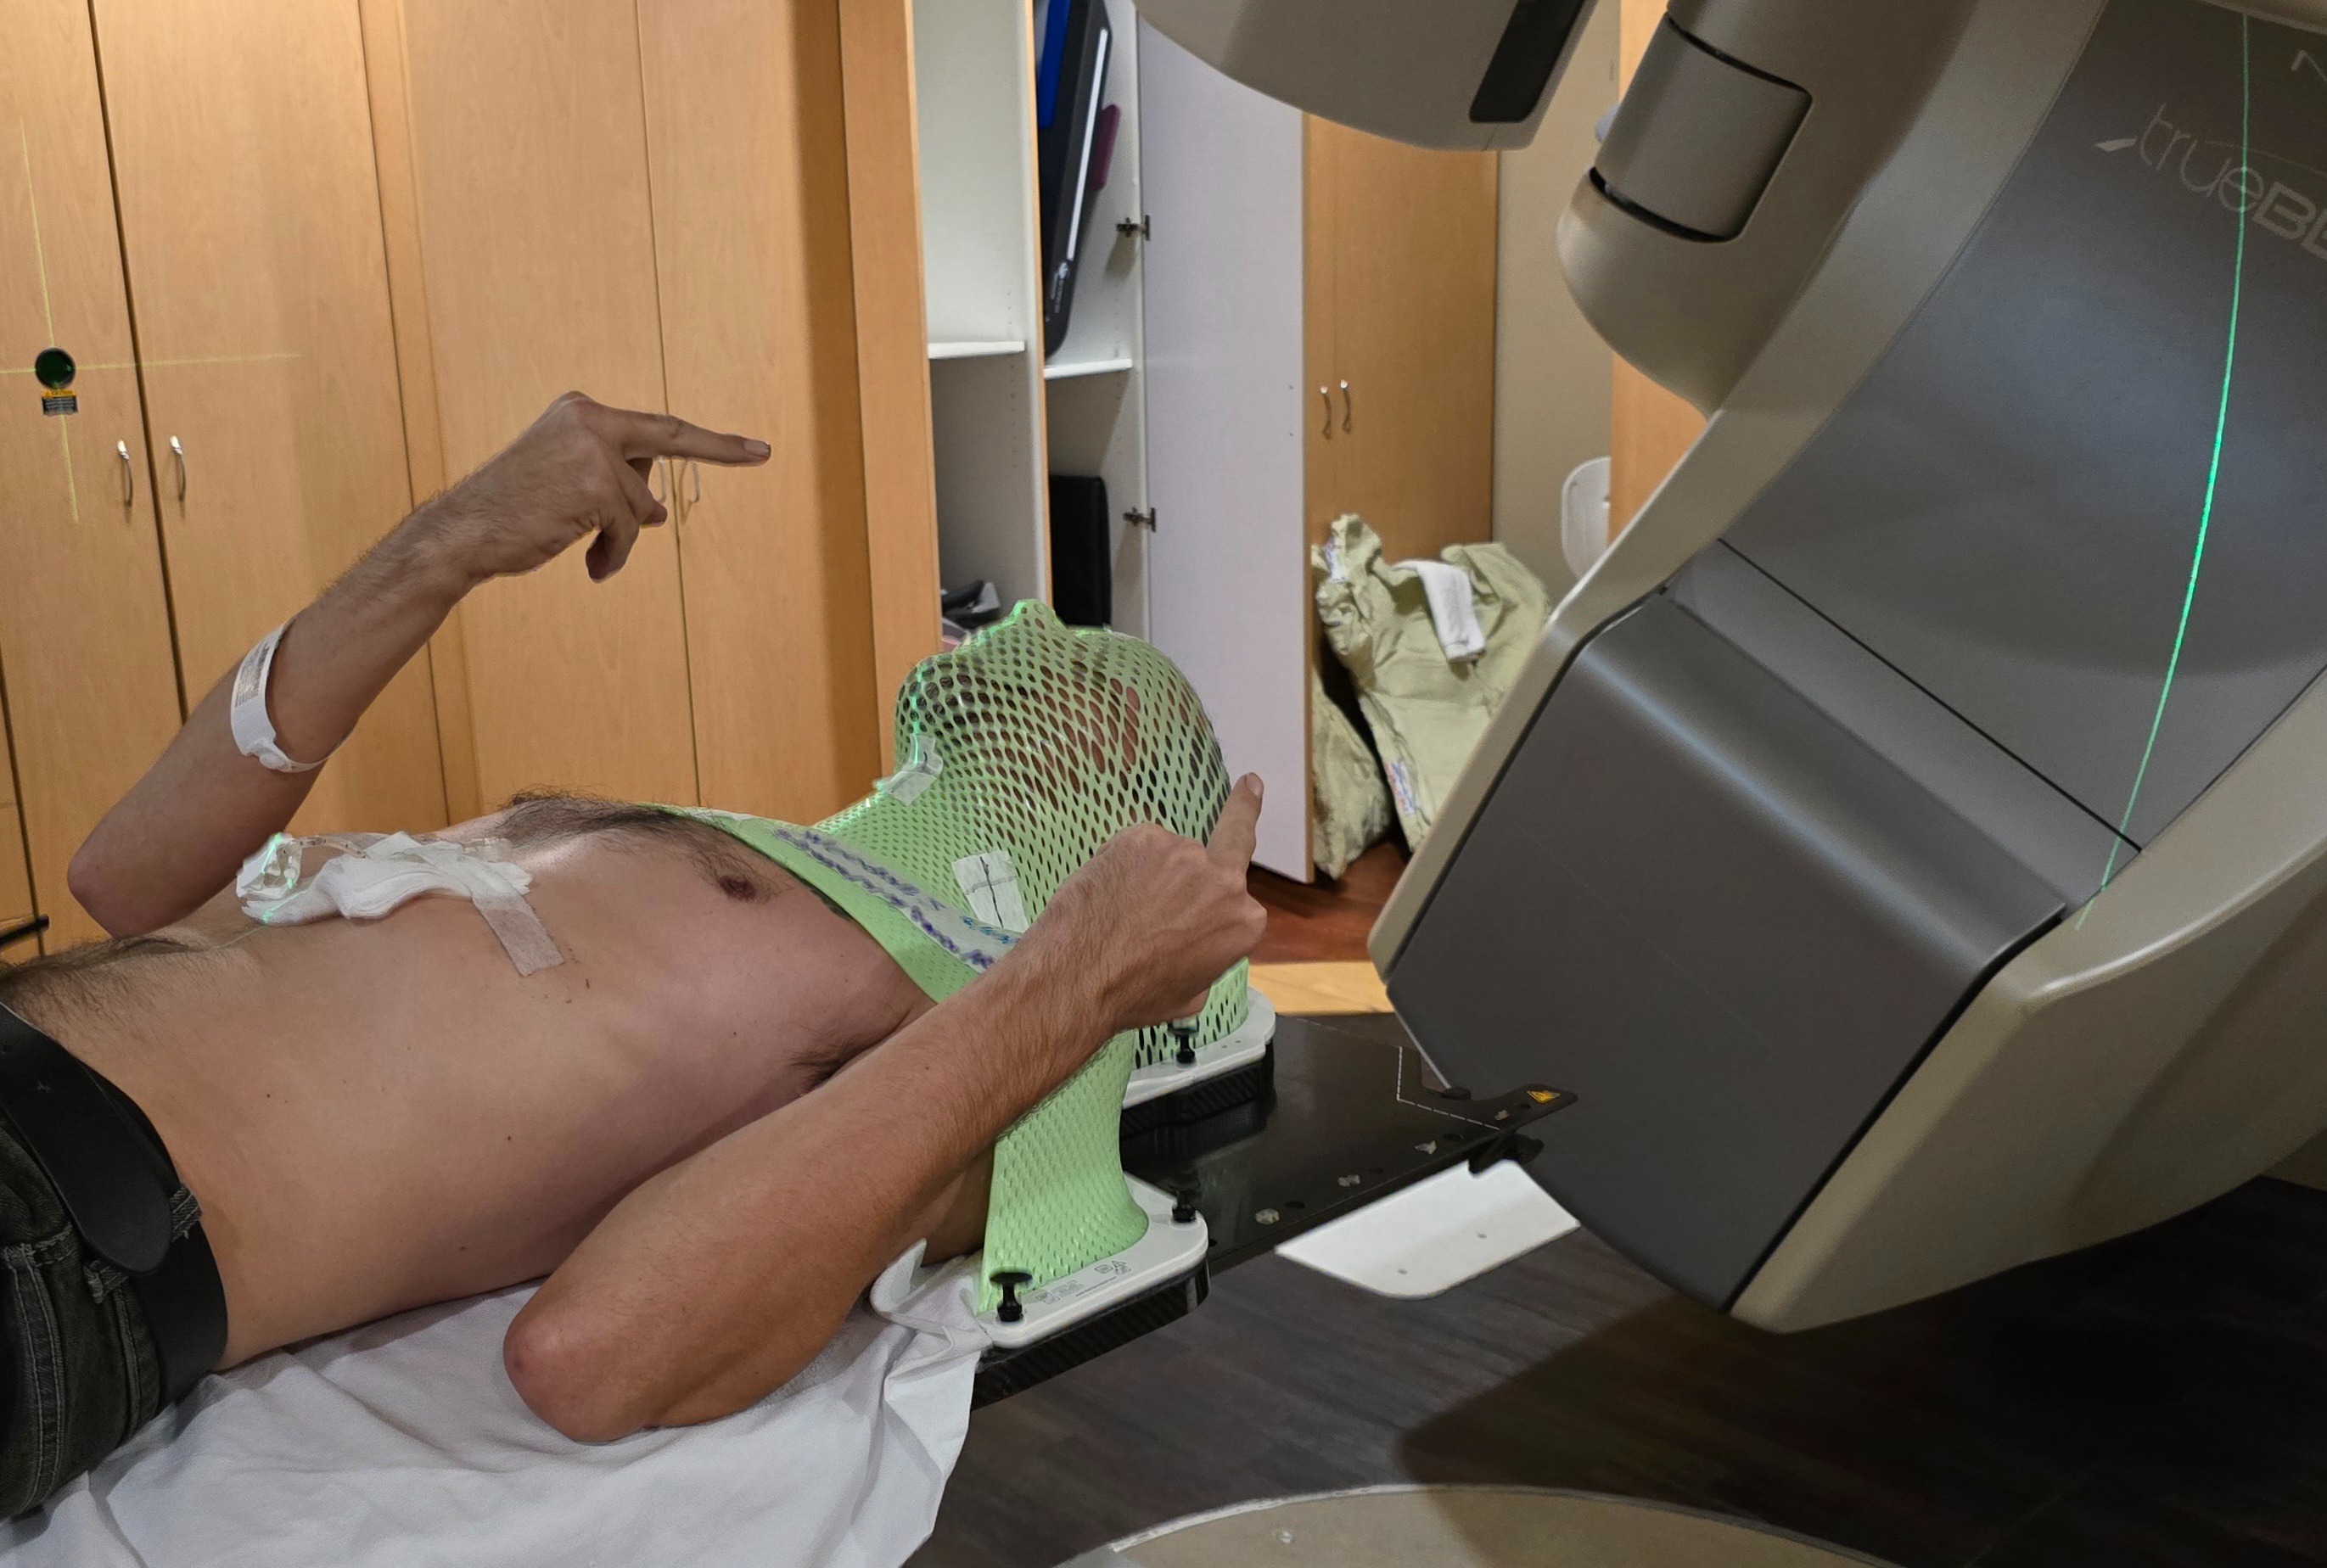

My name is Shane, and on October 30th, I was diagnosed with metastatic poorly differentiated non keratinizing squamous cell carcinoma. Since then, my life has changed dramatically. I am currently undergoing weekly chemotherapy and daily radiation treatments, which has made it impossible for me to work. The physical and emotional toll of treatment is challenging, and the uncertainty about my health and future can feel overwhelming at times.